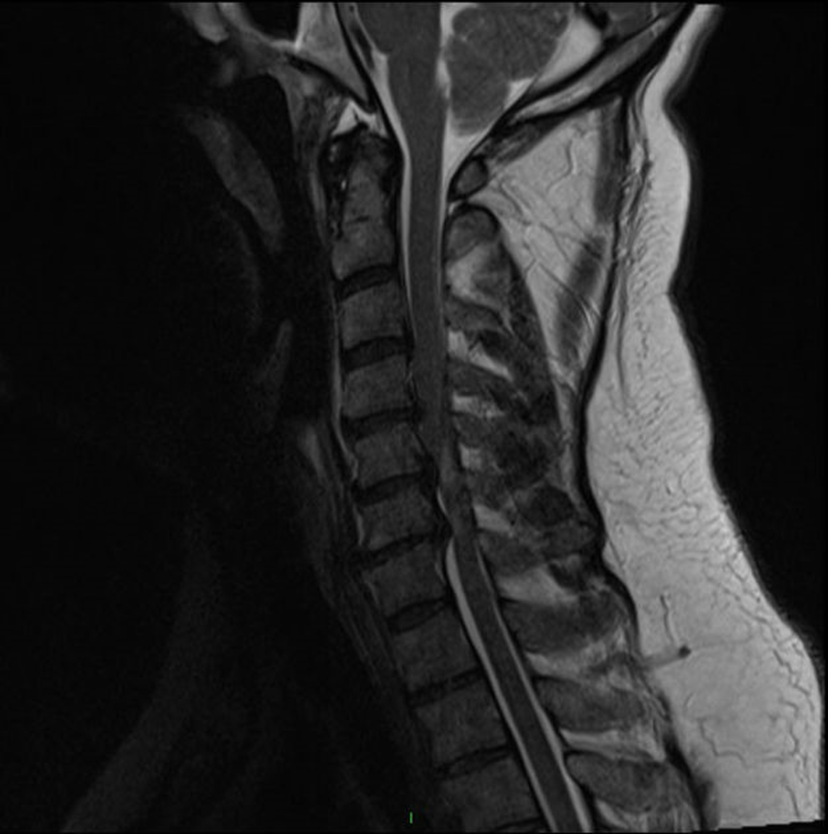

-Tăng tín hiệu bên trong nhu mô tủy sống trên T2WI ở nhiều tầng (hình 1).

Hình 1. Tăng tín hiệu trong tủy sống trên chuỗi xung T2 mặt phẳng sagittal ở vị trí C5-C6, C6-C7 (nguồn: radiopaedia.org).

-Tăng tín hiệu trên T2 ở một tầng kèm giảm tín hiệu trên T1 ở cùng vị trí (tăng tín hiệu trên T2 nhưng không thay đổi tín hiệu trên T1 ở một tầng không có giá trị tiên lượng chắc chắn).

-Teo tủy sống (diện tích cắt ngang <45 mm2 ) Những dấu hiệu khác có thể thấy trên MRI trong CSM: -Giảm diện tích cắt ngang của tủy sống ở tầng bị chèn ép nhiều nhất. Hình ảnh “quả chuối” trên phim cắt ngang (axial) gợi ý khả năng cao bệnh nhân có tình trạng CSM. Có những bằng chứng mâu thuẫn về dựa vào mức độ hẹp của ống sống để tiên lượng kết quả điều trị. Hình ảnh T2WI cắt đứng dọc (Sagittal) có khuynh hướng phóng đại mức độ chèn ép tủy sống do gai xương và/hoặc đĩa đệm, do đó khảo sát trên mặt phẳng ngang (axial) và chuỗi xung T1 là cần thiết để đánh giá tình trạng bệnh lý. Hẹp ống sống không phải là dấu hiệu đặc thù của CSM: khoảng 26% bệnh nhân >64 tuổi không có triệu chứng có hình ảnh chèn ép tủy sống trên MRI.